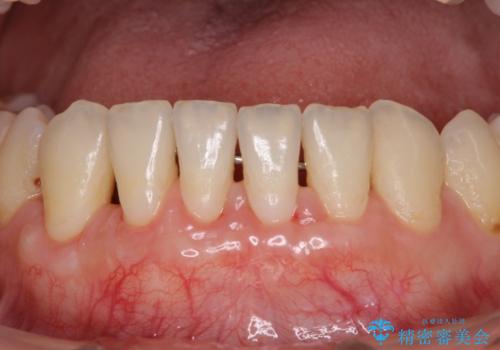

下顎前歯の歯肉退縮 歯肉移植による根面被覆

担当医 藤巻太一朗